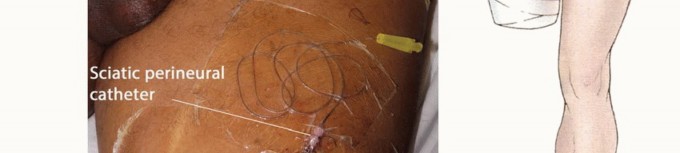

- معالجة الأعصاب: يجب سحب الأعصاب بلطف حوالي 2 سم، وربطها بخيوط غير قابلة للامتصاص، وقطعها بسكين. يمكن استخدام الخيوط لاحقًا لتحديد الأعصاب الفخذية والوركية إذا كان سيتم وضع قسطرة فوق الجافية. إذا لم يتم وضع القسطرة، فيجب السماح للأعصاب بالانكماش مرة أخرى إلى كتلة العضلات.

وضع قسطرة فوق الجافية وربط العضلات Myodesis

- قسطرة فوق الجافية: يتم عمل فتحة صغيرة باستخدام مشرط رقم 15 في غمد العصب. يتم إدخال قسطرة فوق الجافية، تم غسلها مسبقًا بمحلول بوبيفاكايين 0.25%، في الفراغ فوق الجافية وتمريرها باتجاه الأعلى لمسافة 5 إلى 7 سم. ثم يتم إغلاق غمد العصب بخياطة كروميك 4-0. يتم إدخال قسطرة وريدية بحجم 16 في الجلد عند الموقع المطلوب لخروج قسطرة فوق الجافية. يتم تمرير قسطرة فوق الجافية عبر القسطرة الوريدية حتى تصبح مرئية خارج الجلد. يتم إحضار القسطرة الوريدية، التي تحتوي على قسطرة فوق الجافية، بعناية عبر الأنسجة تحت الجلد لتخرج عند الجلد.